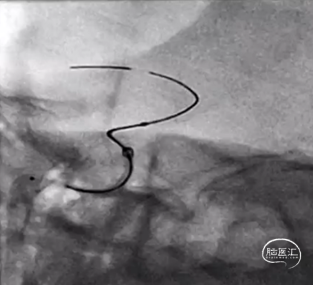

继续缓慢释放Nuva®支架,在血管过弯处及支架尾端释放时注意随时调整系统张力,确保支架完全打开。

【过弯及尾部支架打开良好】

完全释放支架后,工作位造影可见支架显影清晰,形态良好,无贴壁不良,遂采取固定输送导丝,向前推送微导管,待微导管穿过装置后,将输送导丝远端回撤入微导管内,撤出支架输送系统。

为保证Nuva®血流导向密网支架的充分贴壁,支架完全释放后,微导丝弓背进入,进行支架内充分“按摩”,使之充分贴壁。